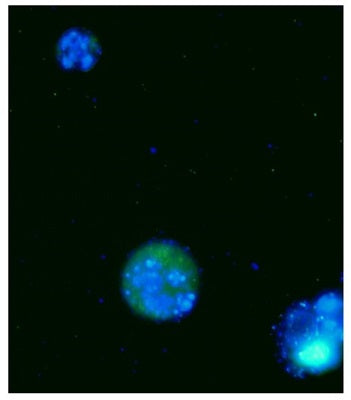

- If desired, label with additional stains, such as Hoechst, Propidium Iodide, 7-AAD, or an antibody.

- Analyze with a fluorescence microscope, fluorescence plate reader, or flow cytometer. FAM-FLICA excites at 492 nm and emits at 520 nm.